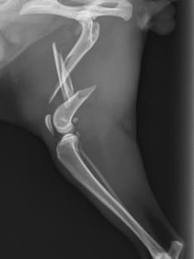

- Radiografia